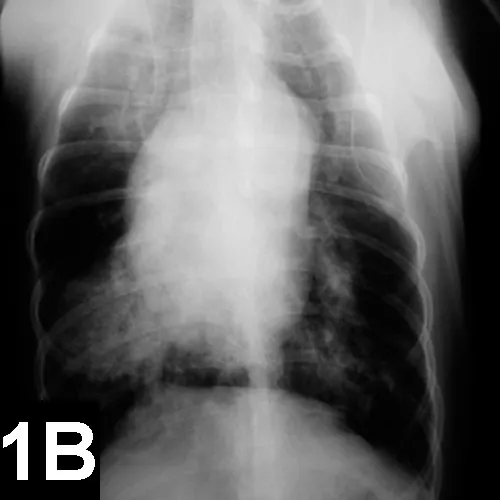

FIGURE 1

Lateral (A) and VD (B) views of a patient with heartworm disease and PTE. Note blunting and enlargement of the pulmonary arteries and the heavy interstitial to alveolar infiltrate.

• In patients with PTE caused by heartworms, thoracic radiography may show signs of blunting and enlarged pulmonary arteries, plus interstitial to alveolar infiltrate (Figure 1).

• In patients with PTE secondary to other underlying disease, radiographs may appear normal.

• Additional findings may include:

• Right-sided heart changes from D immitis infection or pulmonary hypertension

• Areas of lucency and decreased perfusion caused by reduction of pulmonary blood volume

• Pleural effusion

• Interstitial or alveolar infiltrate